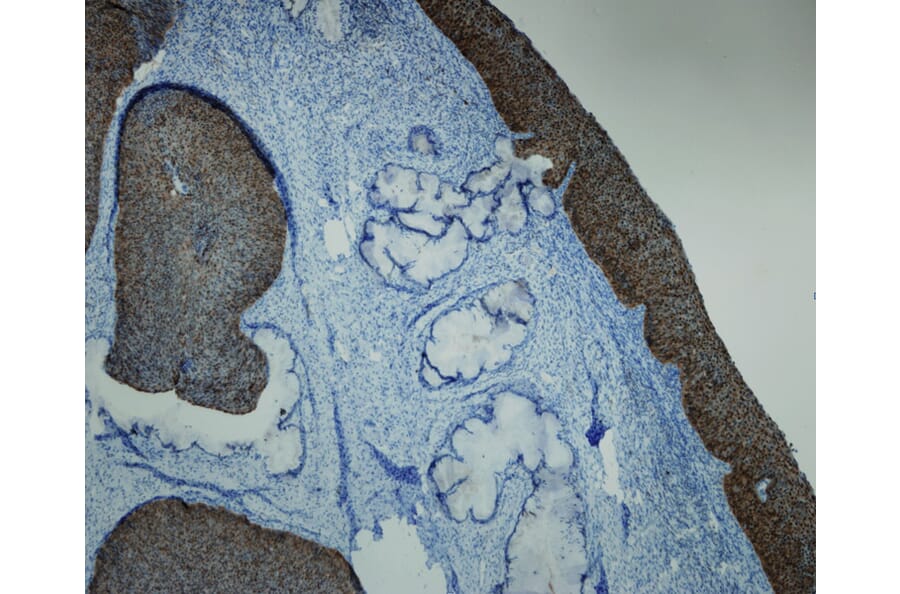

Adenocarcinoma in situ of the uterine cervix, stained with Anti-p16 Antibody (A8237). Shows strong and specific positive immunostaining of dysplastic and neoplastic epithelium, with no reactivity in normal epithelial and stromal structures. Formalin fixed, paraffin embedded human tissues (4µm sections) stained.